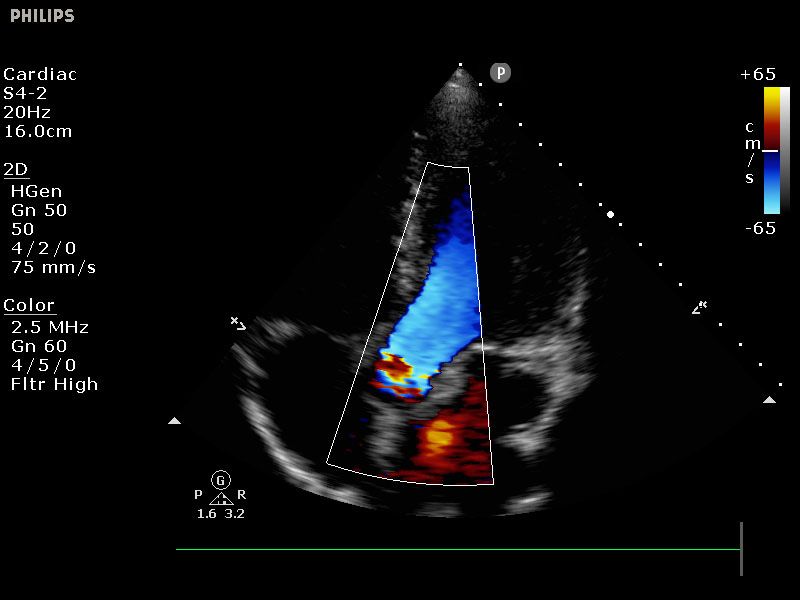

Sparq bietet eine breite Palette klinischer Anwendungen speziell für die Innere Medizin, Notfallmedizin, Intensivversorgung, ultraschallgeführte Regionalanästhesie und Schmerzmedizin, einschließlich Interventionen an Nerven, Wirbelsäule, Muskel-Skelett-System, Gefäßen, Herz und Lunge sowie mittels TEE.